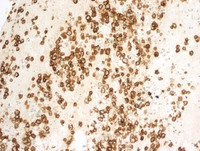

Figure 3: HHV8 in KS lesion

Nuclear staining for HHV8/KSHV/LANA-1 in the KS cells. Infection is universal in KS lesions and is central to the pathogenesis.